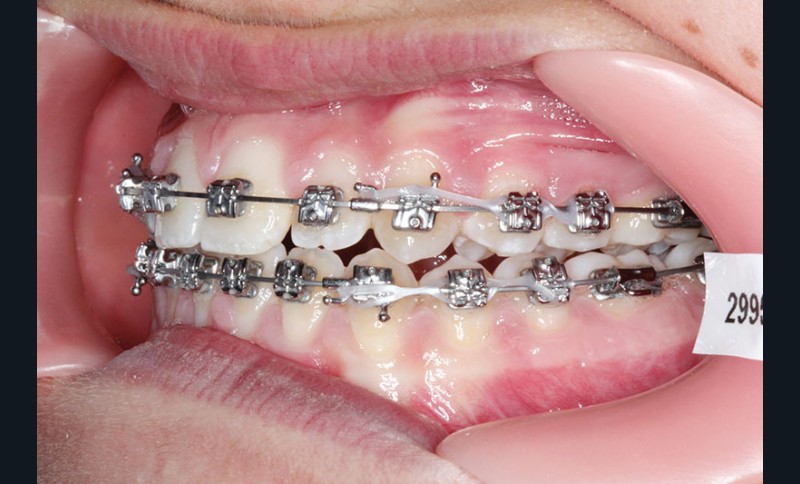

2e phase : mise en place du système multibague Carriere SLX (fig. 7 à 9)

Nous continuons le port des élastiques…